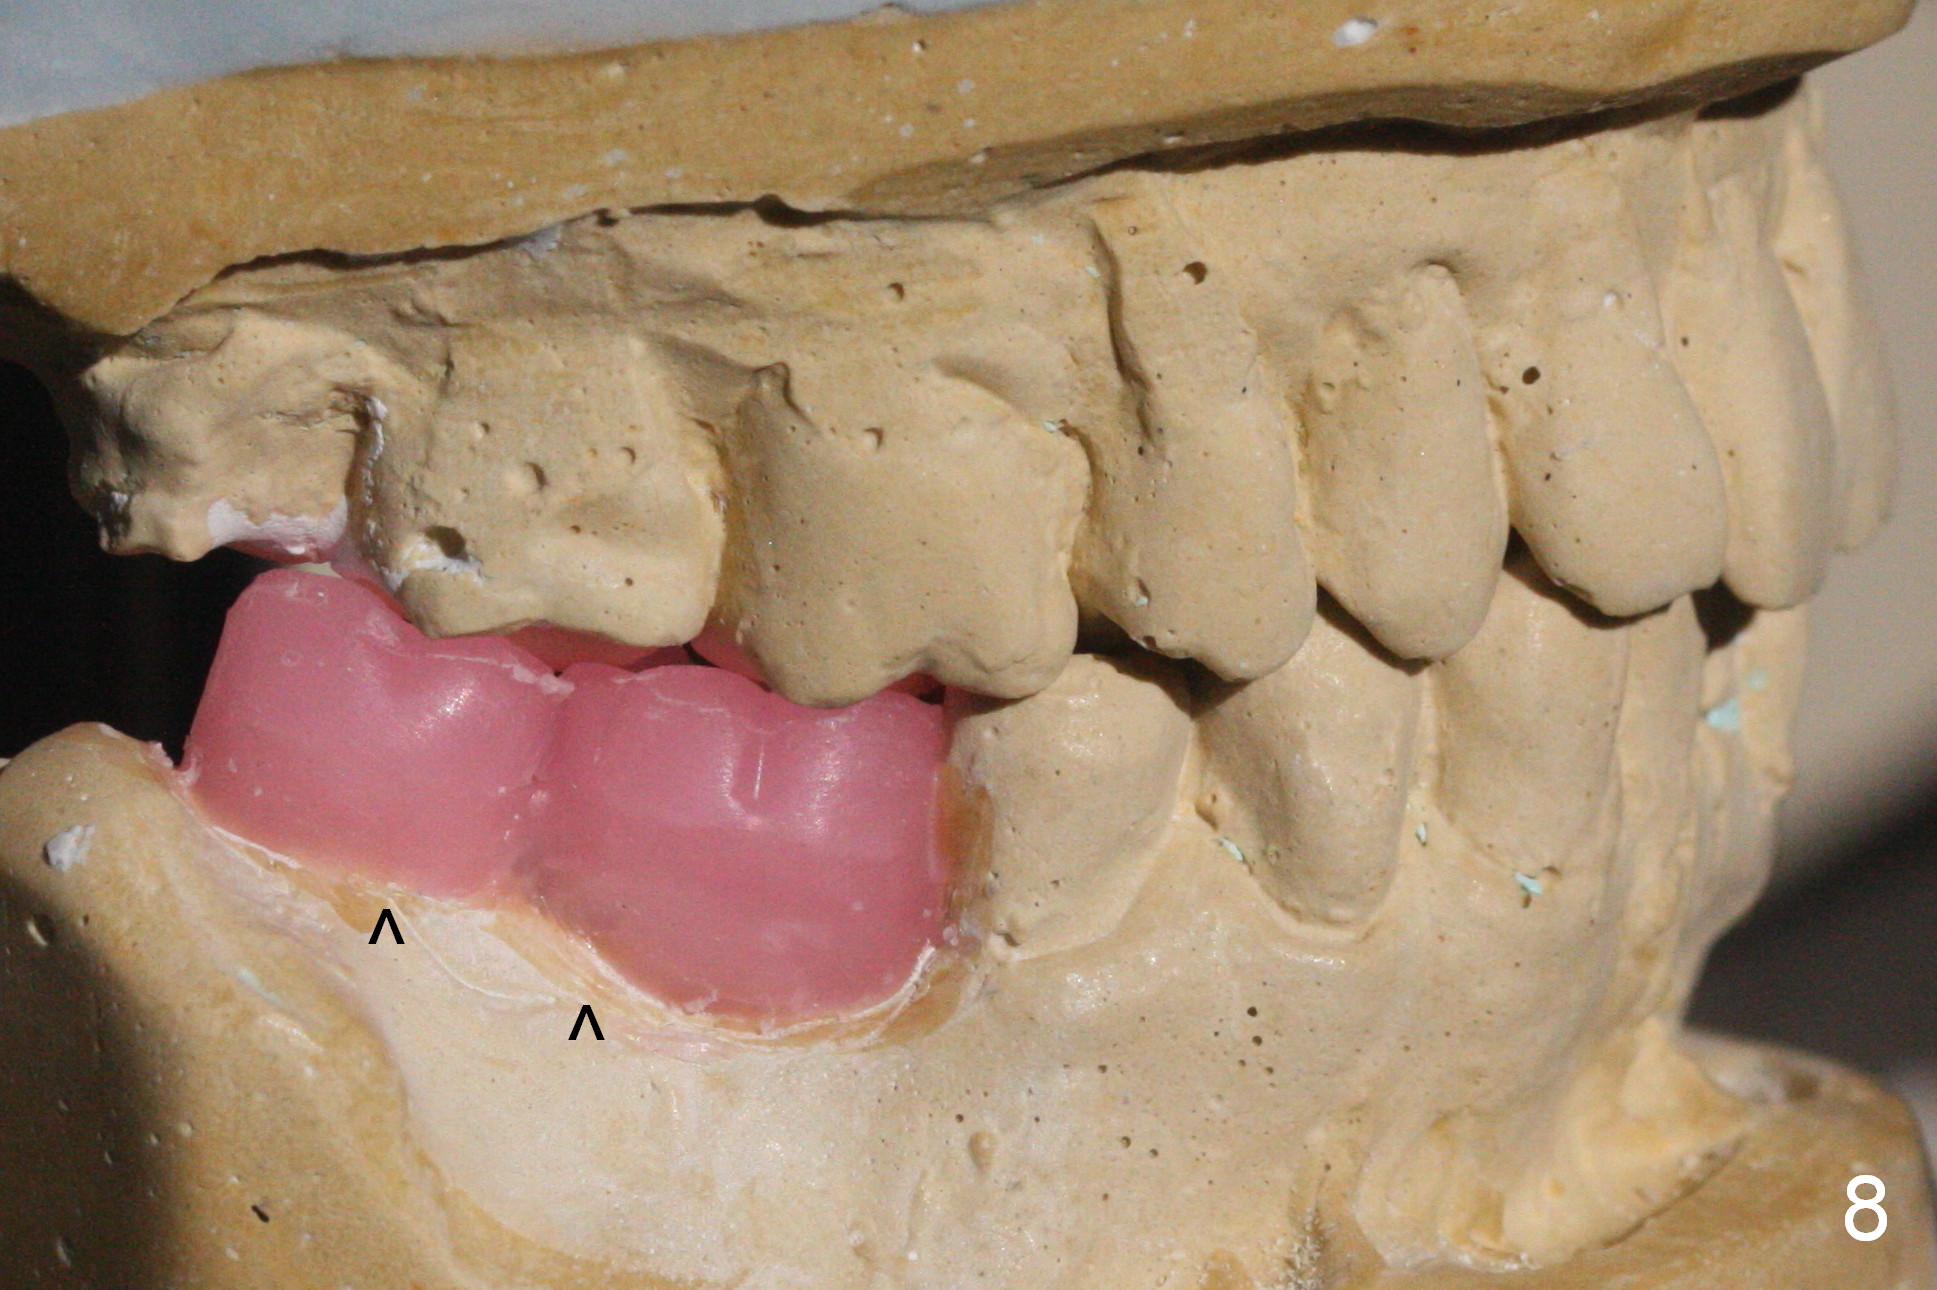

Take Alginate impression and keep it moist. It will be used as a stent for temporization later on. After the tooth #17 is extracted with Clindamycin treatment, a FC dummy implant (5x9 mm) will be placed, followed by 6x4(2) mm abutment (Fig.3,4 pink). If there is severe vertical height issue, change to Magicore. Due to schedule conflict, prepare UF for this case instead.

One of the patient's daughter feels that the treatment is too complicated. She would like to have the 2nd molars extracted and implants at the 1st and 2nd molar sites (from Fig.5,6 to 7-9). Since the upper canines are missing (Fig.5,6), the final occlusion will be Class II posteriorly (Fig.8,9).